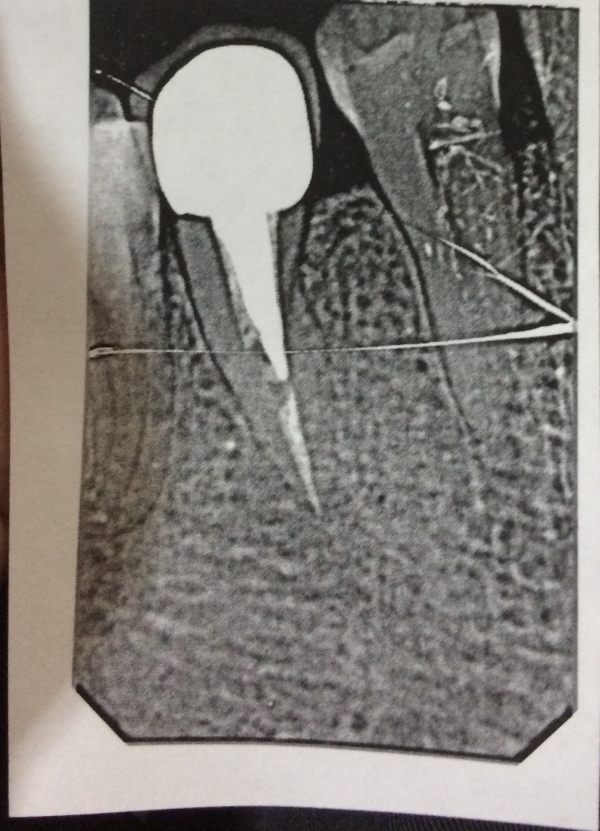

Прикладываю фото 25-го зуба (там 3 фото с иглами до пломбировки каналов и после один был не до пломбирован, сразу добавили на третьем фото. Небольшое воспаление у корня было, его лечили, сказали результат не сразу).

Можно ли на такой зуб поставить вкладку из диоксид циркония? Фактор двухканальности зуба облегчает ситуацию? Как фактор близости к десне и возможного контакта вкладки с тканями зуба влияет на выбор материала культевой вкладки? Можно ли уже заниматься протезированием? Как вы оцениваете лечение корневых каналов? Как относитесь к культевым вкладкам из титана? Какую вкладку мне установить вкладку? Бывают ли вкладки из чистого титана? Может ли быть возможный контакт культевой вкладки с тканями зуба причиной беспокойства?